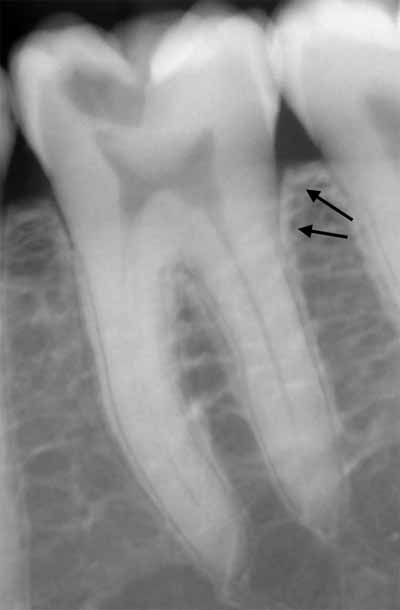

歯の根の周囲には、繊維性結合組織からなる歯周靭帯があります。これは、根の表面に最も近い薄いエックス線透過性の隙間として描画されます。歯周靭帯に最も近い歯槽骨は、歯槽硬線と呼ばれる薄く緻密な骨組織で構成されています。この緻密骨は、歯の根面に沿って歯槽突起の緻密骨と融合する薄いエックス線不透過領域として描かれます (画像3を参照)。

歯槽骨に、薄くわずかに湾曲したエックス線透過性の線が見えることがあります。これらは栄養管であり、神経と血管のための骨内の小さな空洞です (画像5を参照)。多くの場合、上顎洞の壁でもこれらの栄養経路を識別できます。